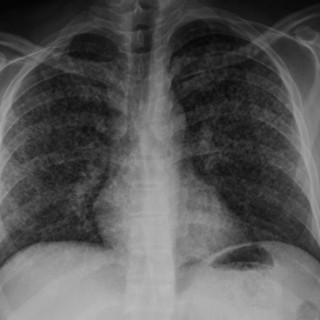

28.01.2010:

HACEK er et akronym som refererer til en gruppe taksonomisk ulike bakterier med en rekke fellestrekk. Det står for Haemophilus parainfluenzae, Aggregatibacter (A aphrophilus, A actinomycetemcomitans), Cardiobacterium spp., Eikenella corrodens og Kingella kingae (1, 2). Alle disse har en tendens til å forårsake endokarditt, men de var tidligere lite kjent fordi de er vanskelige å få til å vokse. HACEK-endokarditt havnet derfor i gruppen kulturnegative endokarditter. Fremdeles forblir mange av disse endokardittene kulturnegative. Bakteriene er små, gramnegative staver tilhørende den...